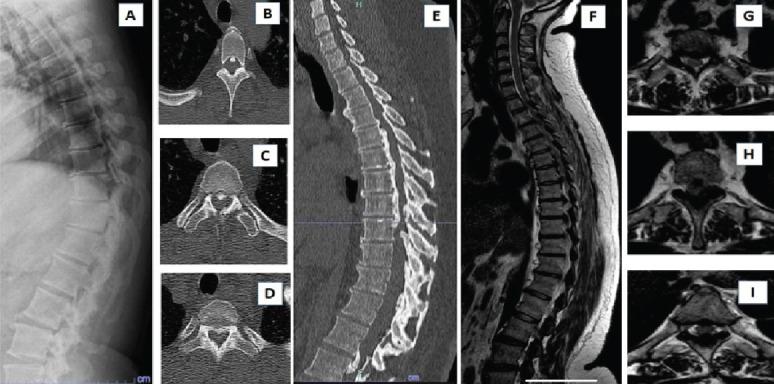

A 45-year-old lady with a body mass index of 33 presented with a long-standing inability to walk due to myelopathy secondary to continuous ossified posterior longitudinal ligament and ossified ligamentum flavum. Posterior fusion and laminectomy were done from D2 to L2. She had an initial wound breakdown with a surgical site infection, but after 6 weeks, she developed spondylodiscitis at the distal instrumented vertebra, leading to DJF. She was started on appropriate antibiotics and an extension of fusion.

This report demonstrates and discusses the management of a rare case of DJF arising due to spondylodiscitis of the last instrumented vertebra.

一名体重指数为33的45岁女性,因连续后纵韧带骨化和黄韧带骨化继发脊髓病,长期无法行走。行D2至L2后路融合及椎板切除术。她最初出现伤口裂开并伴有手术部位感染,但6周后,她在最后固定节段的椎体发生了脊椎椎间盘炎,导致DJF。开始给予适当的抗生素治疗并延长融合范围。

本报告展示并讨论了因最后固定节段椎体的脊椎椎间盘炎引起的罕见DJF病例的处理。